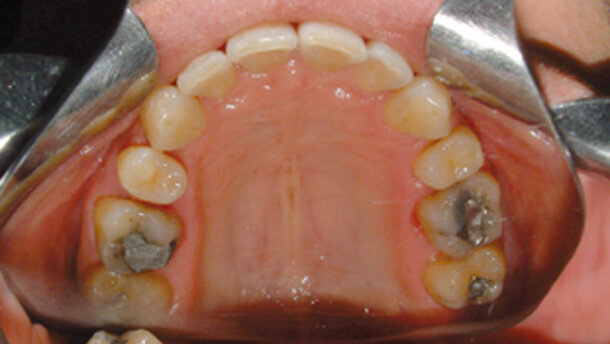

Caso Nº 00561: Apiñamientos y rotaciones en las dos arcadas. Mordida profunda. Tratado con expansión y stripping, e intrusión de los incisivos superiores e inferiores. Arcada superior: 12 pasos. Arcada inferior: 13 pasos.

embedImagecenter("Imagecenter_1_1167",1167, "large");